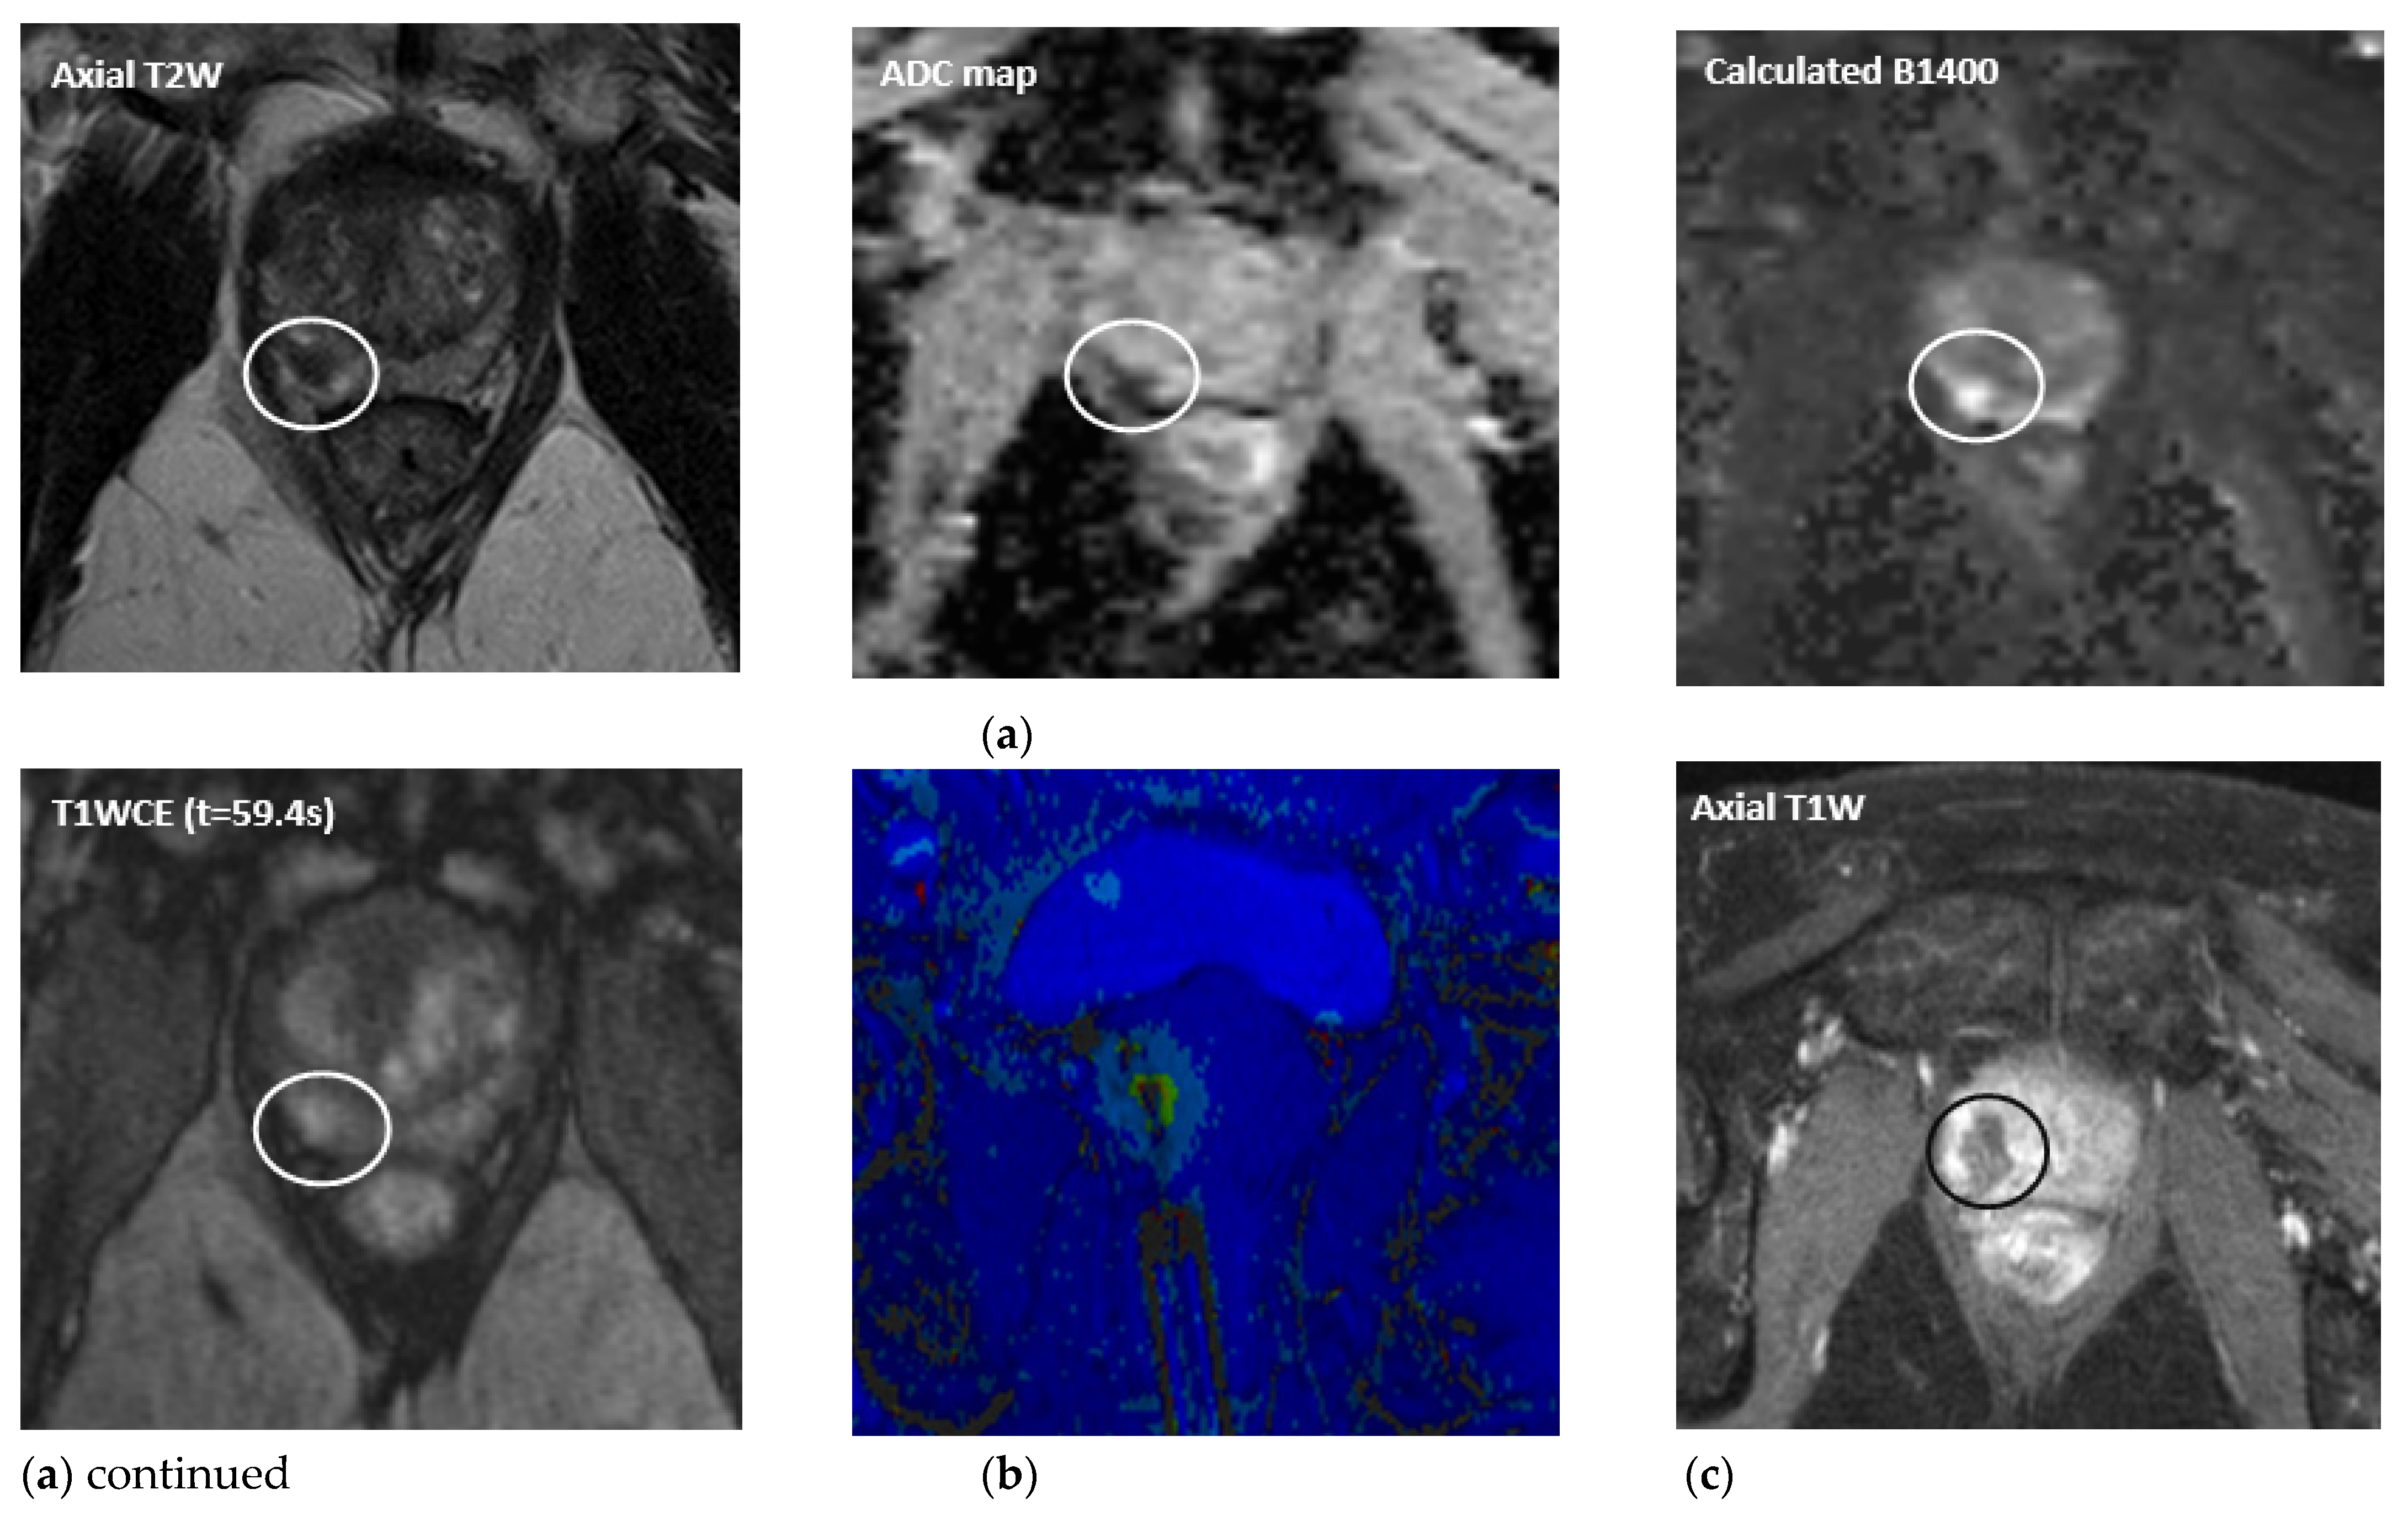

- Napoli, A.; Anzidei, M.; De Nunzio, C.; Cartocci, G.; Panebianco, V.; De Dominicis, C.; Catalano, C.; Petrucci, F.; Leonardo, C. Real-time Magnetic Resonance–guided High-intensity Focused Ultrasound Focal Therapy for Localised Prostate Cancer: Preliminary Experience. Eur. Urol. 2012, 63, 395–398. [Google Scholar] [CrossRef]

- Ghai, S.; Louis, A.S.; Van Vliet, M.; Lindner, U.; Haider, M.A.; Hlasny, E.; Spensieri, P.; Van Der Kwast, T.H.; McCluskey, S.A.; Kucharczyk, W.; et al. Real-Time MRI-Guided Focused Ultrasound for Focal Therapy of Locally Confined Low-Risk Prostate Cancer: Feasibility and Preliminary Outcomes. Am. J. Roentgenol. 2015, 205, W177–W184. [Google Scholar] [CrossRef]

- Ghai, S.; Perlis, N.; Lindner, U.; Hlasny, E.; Haider, M.A.; Finelli, A.; Zlotta, A.R.; Kulkarni, G.S.; Van Der Kwast, T.H.; McCluskey, S.A.; et al. Magnetic resonance guided focused high frequency ultrasound ablation for focal therapy in prostate cancer–phase 1 trial. Eur. Radiol. 2018, 28, 4281–4287. [Google Scholar] [CrossRef]

- Tay, K.J.; Cheng, C.W.S.; Lau, W.K.O.; Khoo, J.; Thng, C.H.; Kwek, J.W. Focal Therapy for Prostate Cancer with In-Bore MR–guided Focused Ultrasound: Two-Year Follow-up of a Phase I Trial—Complications and Functional Outcomes. Radiology 2017, 285, 620–628. [Google Scholar] [CrossRef]

- Ghai, S.; Finelli, A.; Corr, K.; Chan, R.; Jokhu, S.; Li, X.; McCluskey, S.; Konukhova, A.; Hlasny, E.; van der Kwast, T.H.; et al. MRI-guided Focused Ultrasound Ablation for Localized Intermediate-Risk Prostate Cancer: Early Results of a Phase II Trial. Radiology 2021, 298, 695–703. [Google Scholar] [CrossRef]